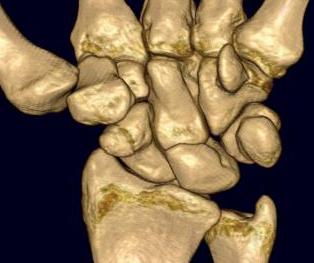

Scaphoid proximal pole fracture

Proximal pole fractures

Chong et al J Plastic Surg Hand 2022

- meta-analyis of proximal third fractures

- nonunion rates 2 - 3X higher than waist fractures

- nonoperative nonunion: 18%

- operative nonunion: 6%

CT

Indication: any potential displacement

Instability

- proximal pole fractures